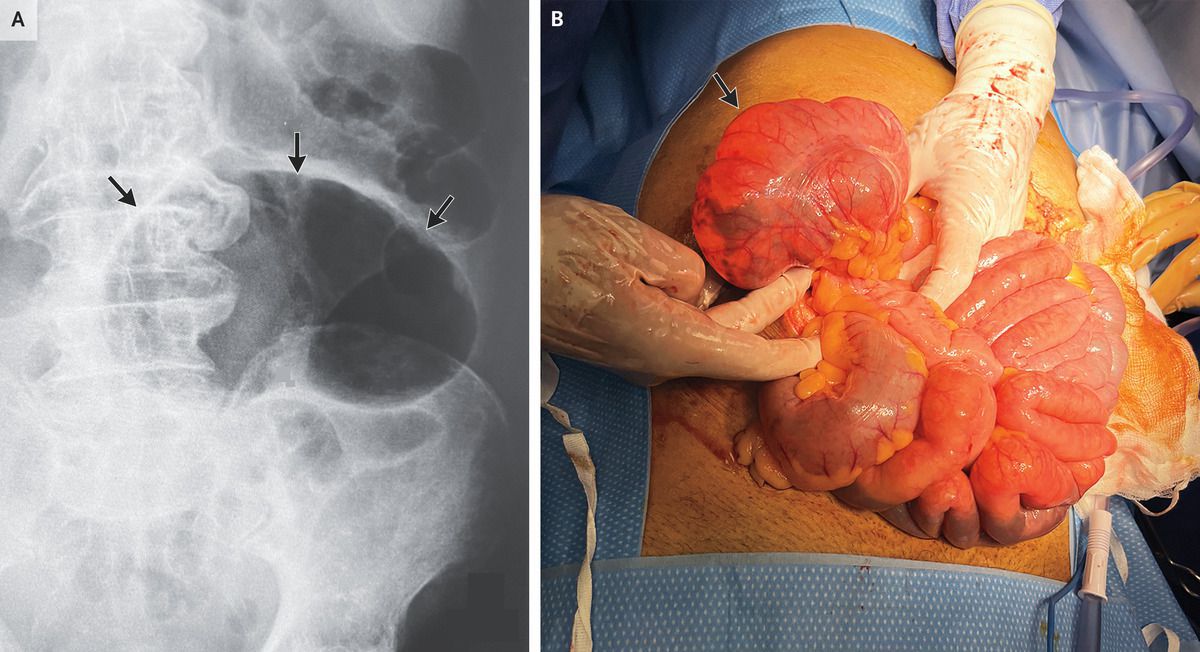

Coffee Bean Sign Volvulus . The proximal large bowel is also dilated (asterisks). The sigmoid colon is very dilated because it is twisted at the root of its mesentery in the left iliac fossa (lif). Specific signs, including a bent inner tube or a coffee bean sign, are characteristics of sigmoid. The coffee bean sign (also known as the kidney bean sign or bent inner tube sign) 4 is a radiological finding on an abdominal plain radiograph of a sigmoid volvulus although. Learn how to recognize sigmoid volvulus on abdominal imaging with the coffee bean sign and the whirl sign. [1] the coffee bean is: Abdominal radiography revealed a markedly distended loop of bowel measuring approximately 17 cm in diameter, consistent with what is known as the “coffee bean. Large bowel folded over itself and twisted in away that creates two. The twisted loop of sigmoid colon is said to resemble a coffee bean.

Coffee Bean Sign Volvulus Large bowel folded over itself and twisted in away that creates two. The proximal large bowel is also dilated (asterisks). Learn how to recognize sigmoid volvulus on abdominal imaging with the coffee bean sign and the whirl sign. Large bowel folded over itself and twisted in away that creates two. The coffee bean sign (also known as the kidney bean sign or bent inner tube sign) 4 is a radiological finding on an abdominal plain radiograph of a sigmoid volvulus although. Specific signs, including a bent inner tube or a coffee bean sign, are characteristics of sigmoid. The twisted loop of sigmoid colon is said to resemble a coffee bean. Abdominal radiography revealed a markedly distended loop of bowel measuring approximately 17 cm in diameter, consistent with what is known as the “coffee bean. [1] the coffee bean is: The sigmoid colon is very dilated because it is twisted at the root of its mesentery in the left iliac fossa (lif).

Coffee Bean Sign Volvulus The sigmoid colon is very dilated because it is twisted at the root of its mesentery in the left iliac fossa (lif). [1] the coffee bean is: The proximal large bowel is also dilated (asterisks). The twisted loop of sigmoid colon is said to resemble a coffee bean. Abdominal radiography revealed a markedly distended loop of bowel measuring approximately 17. Coffee Bean Sign Volvulus.